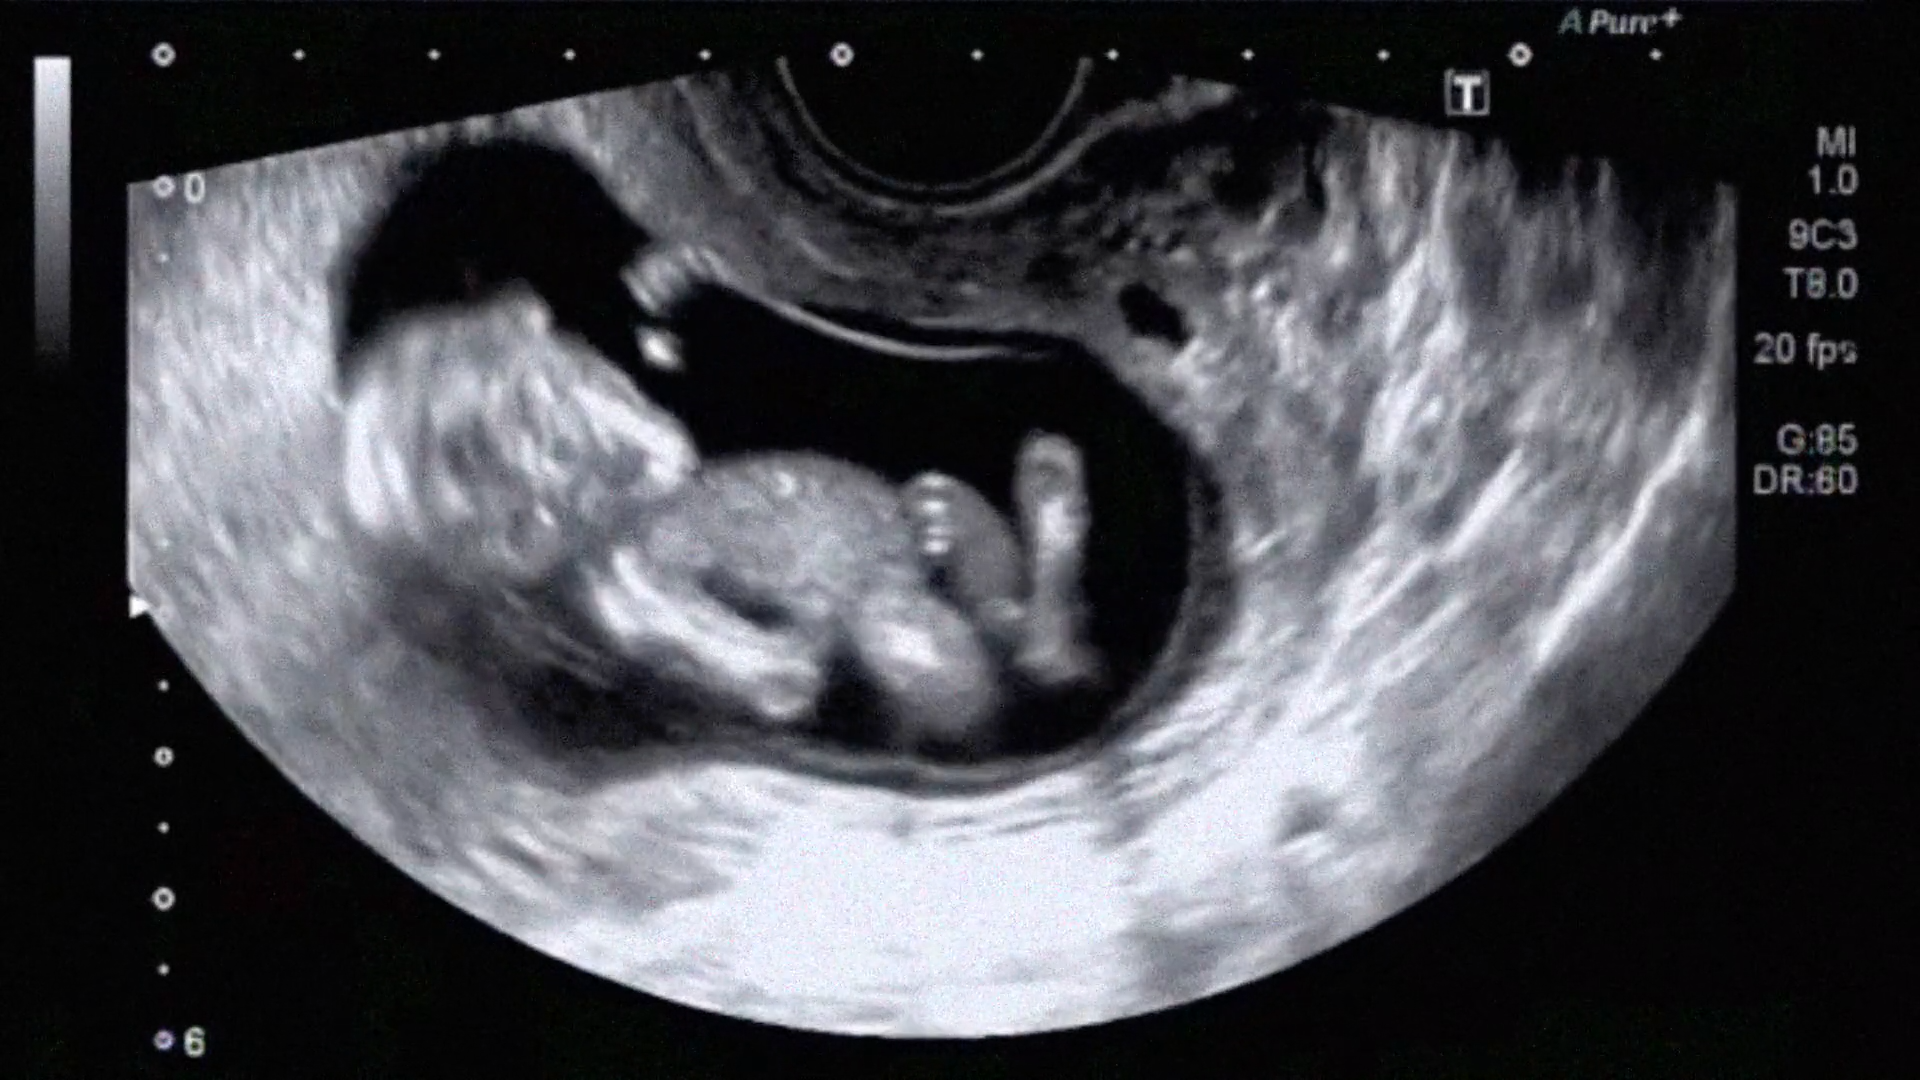

Quand il découvre qu'il va être père, João décide de rechercher l'accouchement qui conviendra le mieux à la mère et l'enfant. L'accouchement humanisé retient son attention.